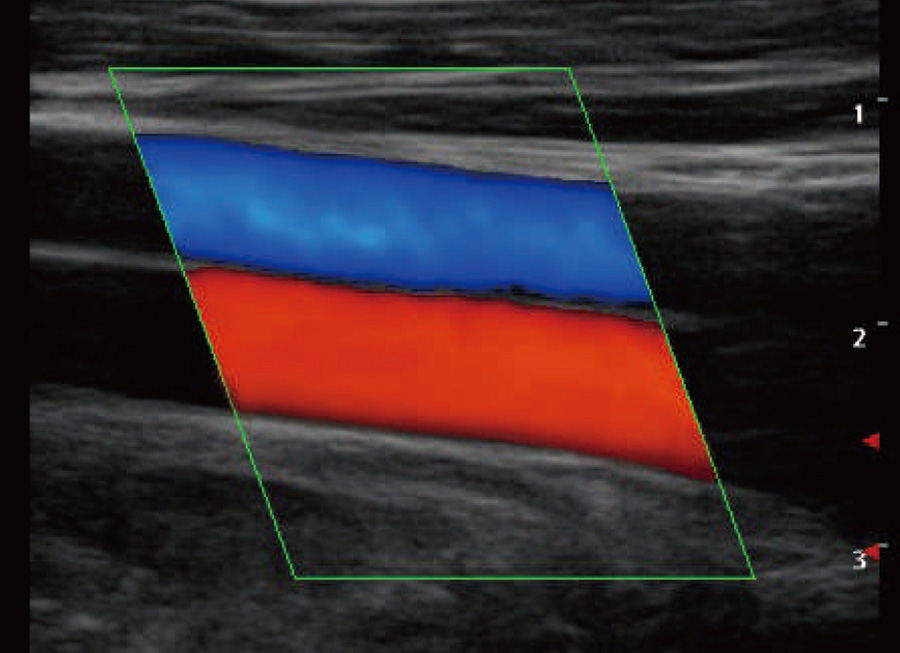

- Wide-ScanWith wide-scan, the ultrasound image can be enlarged when performing a real time scan when using linear or convex probes, for a larger, more complete view of large lesions.

With real-time panoramic, you can acquire an extended field of view for large organ or long vessel for easy measurement and diagnostic efficiency.